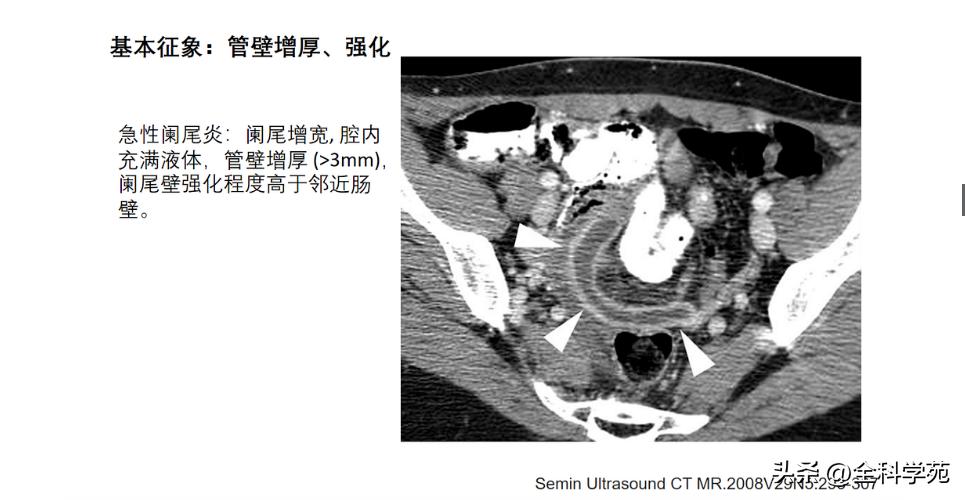

◆ 阑尾壁增厚

>3mm

CT: 阑尾壁明显增强

MRI: T1低信号,T2高信号,DWI: 扩散受限

6-10 mm 伴阑尾壁增厚、壁明显强化,周围脂肪间隙模糊或分层(靶征或牛眼征,表明粘膜下水肿的液体含量vs 气体含量